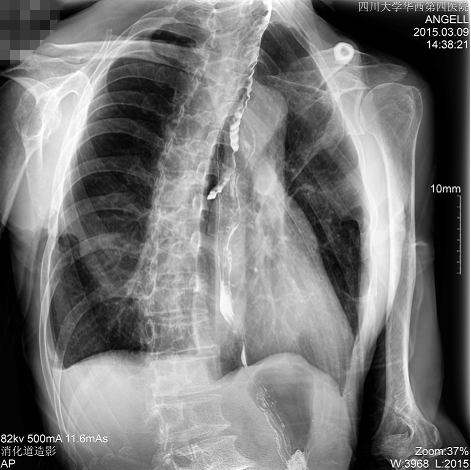

如下图所示:该患者因吞咽时感到很难受,进食时也经??人怨示鸵秸锒稀J褂枚喙δ躣r为病人进行消化道造影诊断,要求他吞钡后发现,食道各段通过顺利,形态规则,双侧梨状窝不对称左侧稍浅,多次吞咽动作后,仍见钡剂滞留,并见钡剂进入气管,属于会厌征阳性?;嵫峁δ芪陕?,钡剂进入了气管。

图为正位:通过动态影像可以清楚看到钡剂进入了支气管道且双侧梨状窝不对称

通过多功能dr可以诊断该病人的症状为会厌功能紊乱,钡剂进入到了气管。而在动态透视下可以清晰的观察到钡剂从何处进入气管,可清晰显示食管粘膜结构。使用多功能dr其独特的视频采集技术,可实时保存视频并能实现900万像素实时点片,才能获取这样清晰的病灶点。而常规dr只能拍摄静态片,且成像效果大打折扣,因此较难确诊病灶。